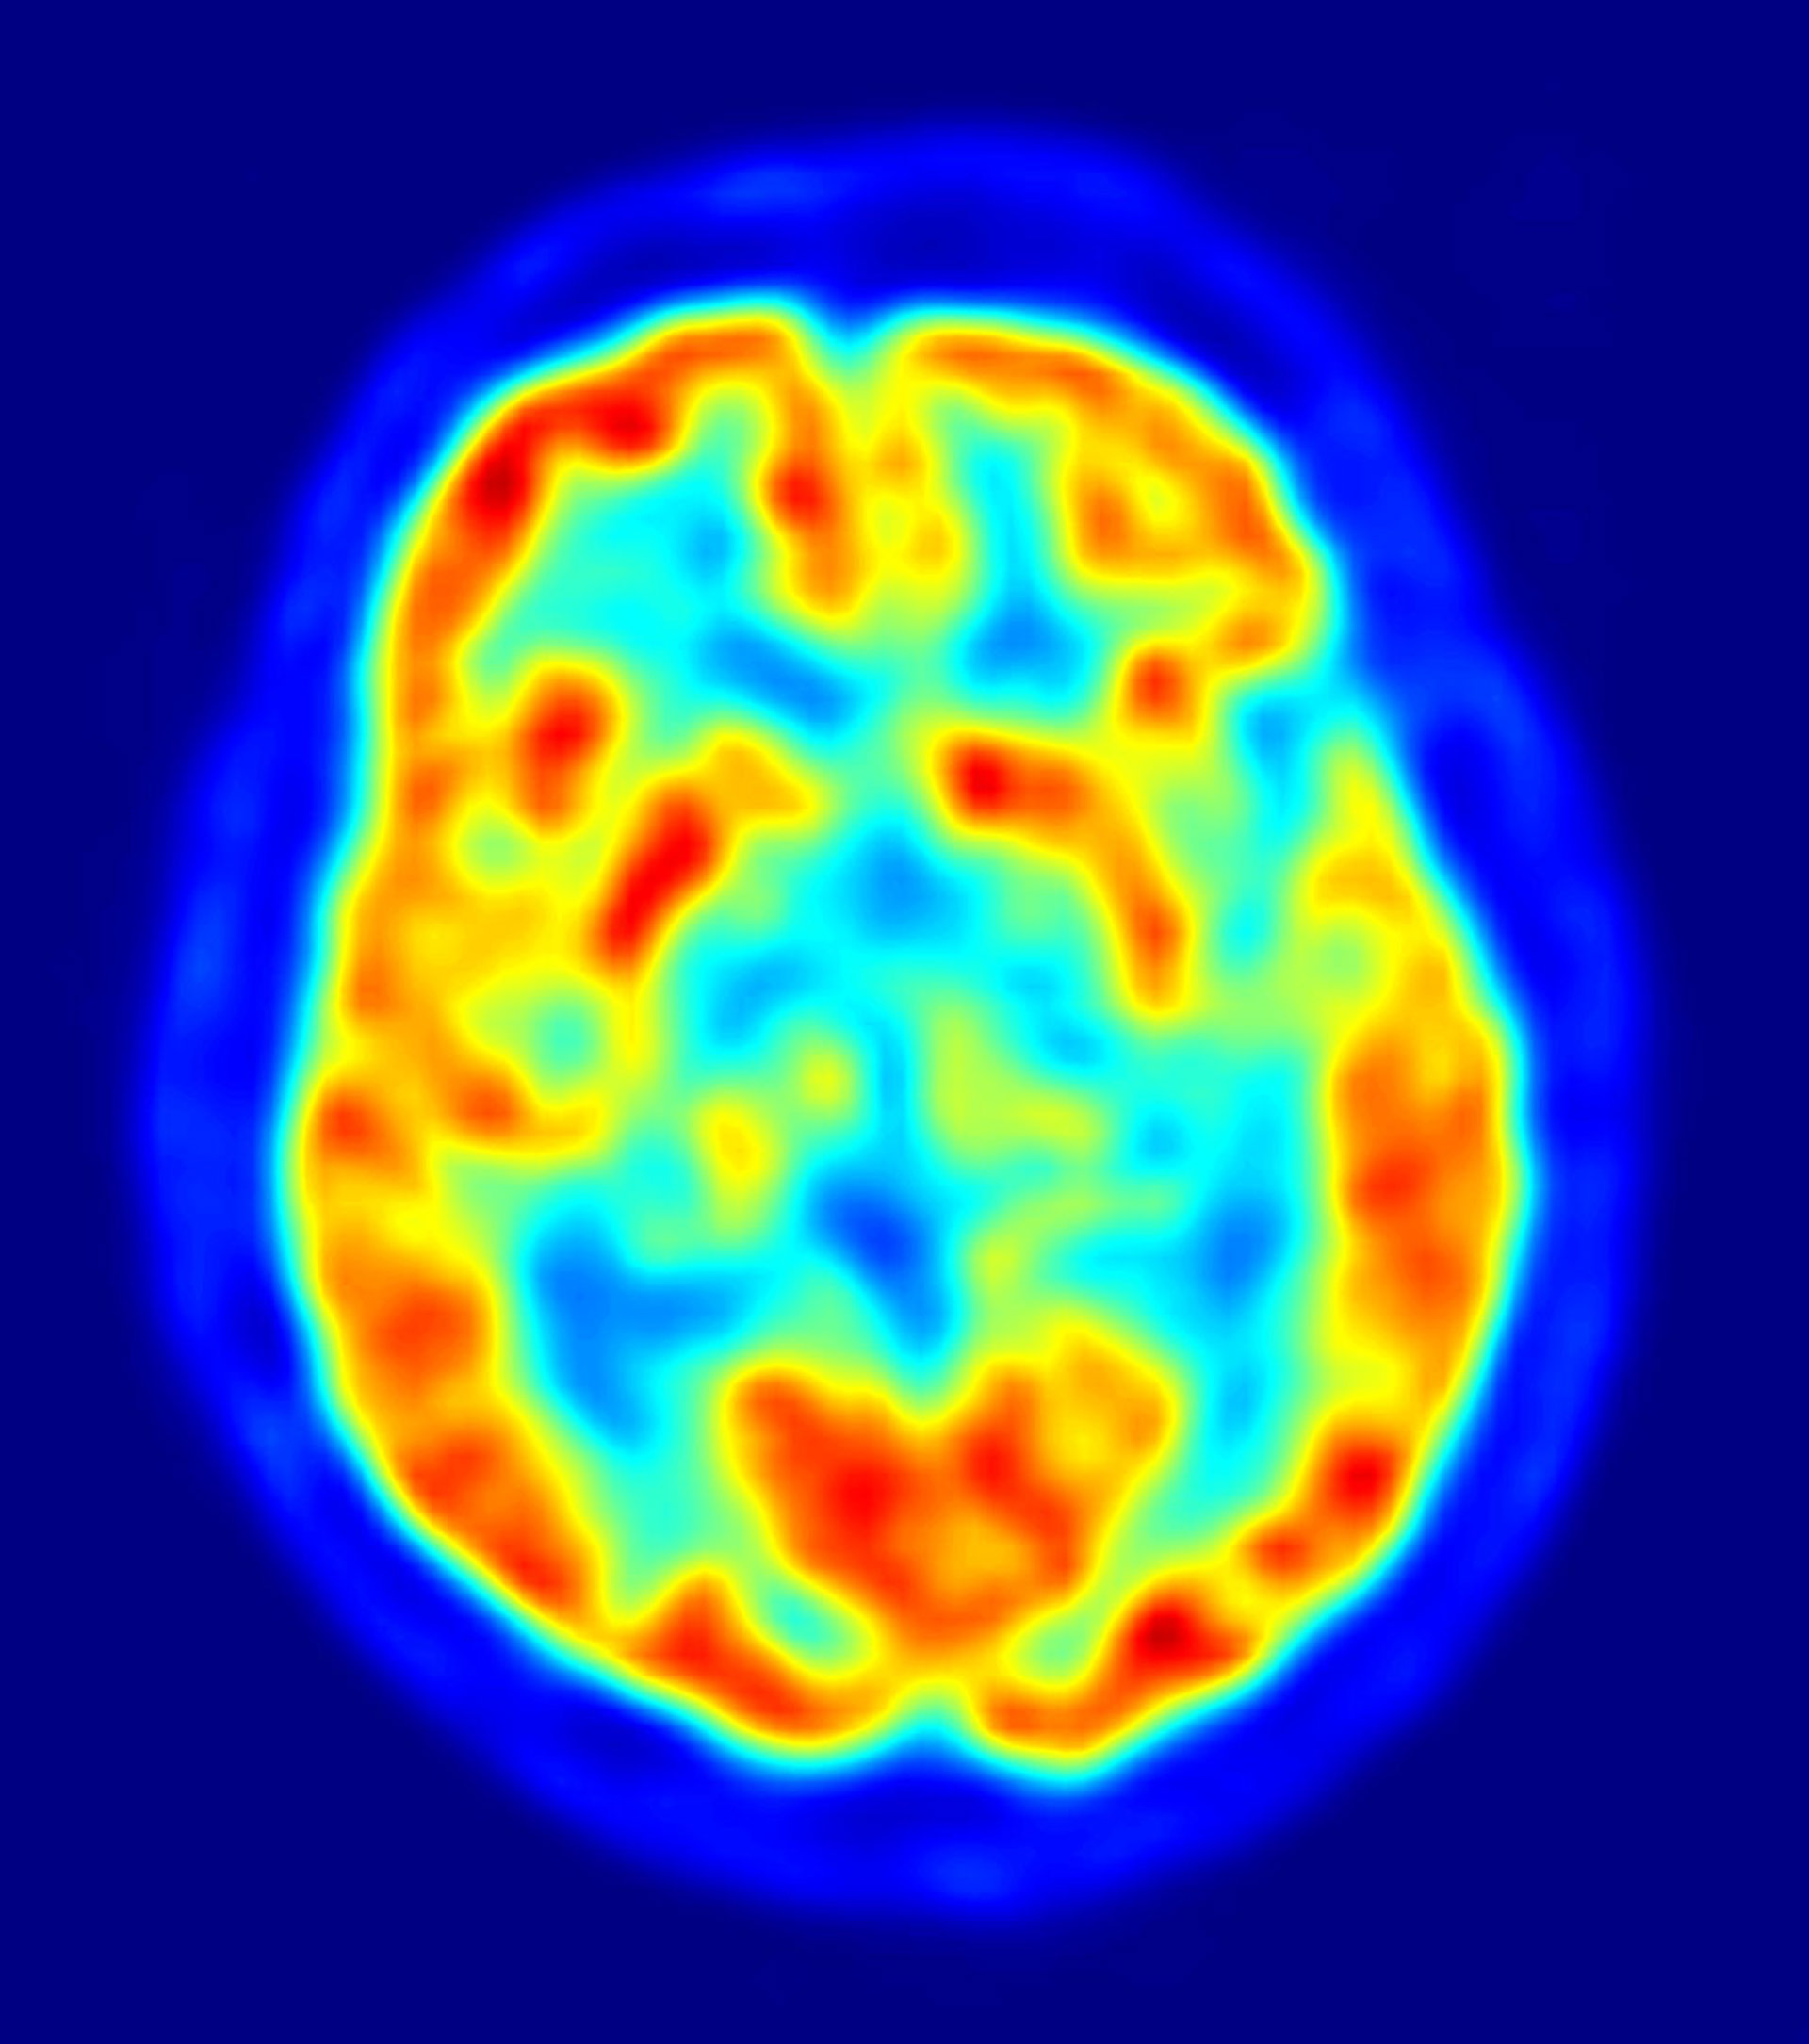

La enfermedad de Alzheimer, la forma más común de demencia, es un trastorno neurodegenerativo con una alta prevalencia entre los mayores.

Los trabajos así subrayan mecanismos moleculares que podrían estar implicados en la neurodegeneración y la eliminación en el cerebro del amiloide beta, el principal constituyente de las placas amiloides que se forman en el cerebro y que caracterizan a la enfermedad de Alzheimer.